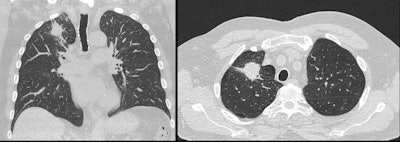

The onboard screening is aimed at current and retired mine and quarry workers and their families who live in regional and remote areas of Queensland with limited access to screening programs. So far, over 500 retired mine workers have been screened and among these, radiologists have identified lung nodules requiring follow-up, suspected lung cancer, as well as emphysema and pneumoconioses. Among younger dust-exposed workers in their twenties and thirties, cases of accelerated silicosis have been identified. These patients undergo a separate screening program accessible via the truck.

The high-resolution chest CT scan performed for the lung screening program uses Philips' Precise Image AI image reconstruction application in addition to iterative reconstruction methods. Together, they reduce radiation dose through automatic centering, based on the size and density of the patient for patient-specific radiation dose customization. The dose is adequately low for the screening program whilst still maintaining image quality.

The adoption of Philips' Precise Image dose reduction package, based on artificial intelligence (AI) algorithms, meant that radiation dose was reduced by a further 50%. The average radiation dose is now around 1.5 mSv for a multiphase high-resolution chest CT scan, according to Jones.

"The 128-slice Incisive CT Pro with a 4-cm detector width has a fast rotation speed of 0.35 seconds. It also has Precise Image that allows for high-quality imaging at very low radiation dose, a first of its kind on a mobile service," Hubbard noted. "Precise Image is the industry's fastest AI reconstruction. It uses convolutional neural networks to generate noise-reduction images. Reducing image noise increases low-contrast detectability, allowing for reduced dose and improved image quality."